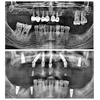

Implant tedavisi